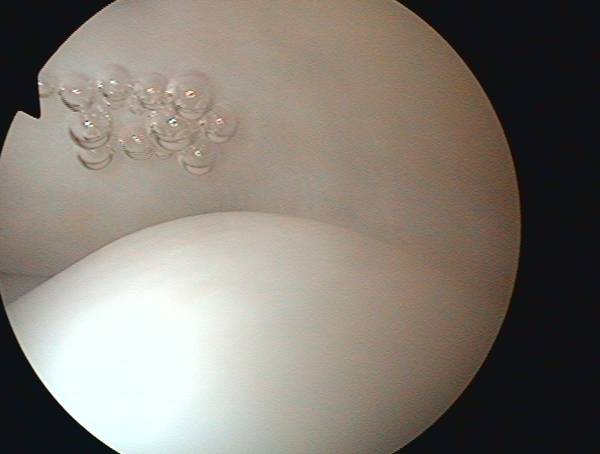

oben: intakte Rotatorenmanschette, unten: gesunder Knorpel des Oberarmkopfes

Der Eingriff erfolgt minimal-invasiv (arthroskopisch) Zunächst werden entzündliche Veränderungen entfernt und der eingeengte Knochenkanal zum späteren Schutz der Sehne erweitert. Im Anschluß daran wird die gerissene Sehne repariert (Rotatorenmanschettennaht, Sehnennaht, Rotatorenmanschettenrekonstruktion). Bei größeren Defekten erfolgt dies über einen zusätzlichen kleinen Hautschnitt.